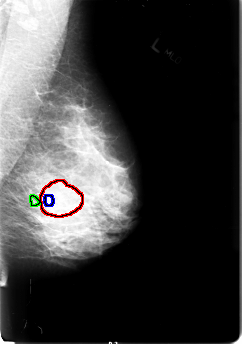

FILE: B_3034_1.LEFT_MLO.OVERLAY

TOTAL_ABNORMALITIES 3

ABNORMALITY 1

LESION_TYPE MASS SHAPE LOBULATED MARGINS OBSCURED

ASSESSMENT 3

SUBTLETY 2

PATHOLOGY MALIGNANT

TOTAL_OUTLINES 1

BOUNDARY

ABNORMALITY 2

LESION_TYPE CALCIFICATION TYPE PUNCTATE DISTRIBUTION CLUSTERED

ABNORMALITY 3